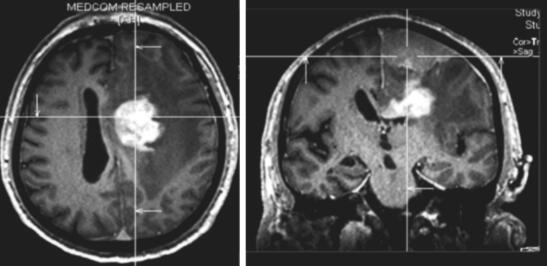

患者,男性,80岁,因“发现左额占位5年,进行性失语1月余”入院。患者于5年前体检时发现左额占位(图1),T1等信号T2等信号,未进一步行增强检查。患者外院就诊考虑患者脑膜瘤可能大,结合患者年龄建议保守治疗密切随访。患者之后未定期就诊复查头颅MRI。患者自1个月前开始出现言语迟缓,主要表现为言语表达困难,无言语理解障碍,进行性加重,伴右侧肢体肌力进行性减退,左侧肢体肌力未受影响。患者就诊外院后进一步查头颅MRI提示左额多发病灶,浅部病灶明显均匀强化,考虑患者既往病史考虑脑膜瘤可能大;深部病灶不均匀强化,伴坏死,高级别胶质瘤不能除外(图2)。患者进一步查头颅FDG-PET提示左额浅部病灶放射性摄取值轻度增高,SUV值最大8.9,结合病史,考虑颅内原发低代谢肿瘤(脑膜瘤可能大);左额深部侧脑室上方病灶放射性摄取异常增高,SUV最大值21.6,考虑脑内原发恶性肿瘤可能大,体部PET显像未见FDG代谢明显异常增高(图27-3)。患者入院后积极完善相关检查,排除手术禁忌后行左额浅部病灶切除+深部病灶活检术,术中冷冻结果提示左额浅部病灶为脑膜瘤,深部病灶为小圆细胞恶性肿瘤。

图2 患者2017年复查头颅MRI增强提示左额多发病灶,浅部病灶明显均匀强化;深部病灶不均匀强化,伴坏死